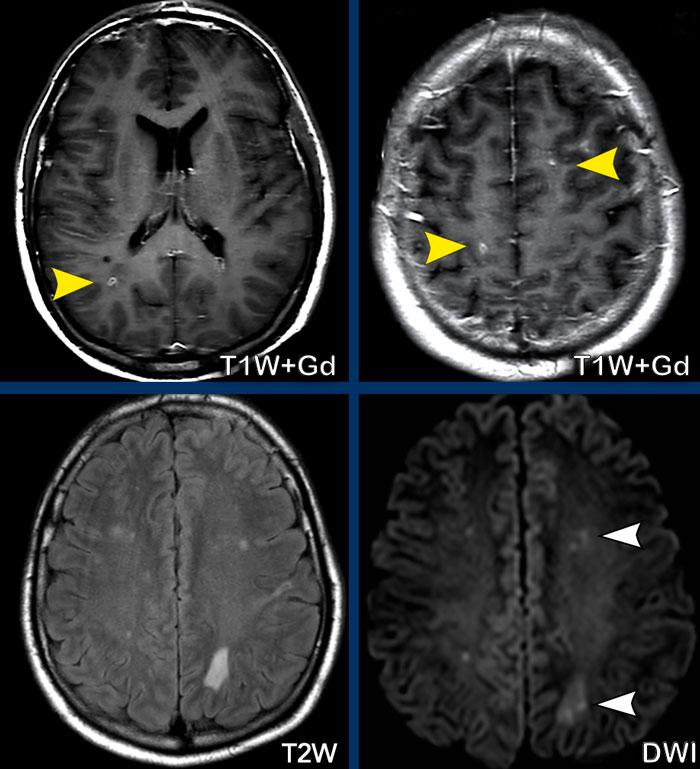

Thuyên tắc nhiễm khuẩn

Bốn hình ảnh này của một bệnh nhân trẻ bị nhiễm khuẩn huyết do phế cầu khuẩn, diễn tiến nặng và hôn mê.

Hình ảnh

Có các nốt nhỏ ngấm thuốc (đầu mũi tên vàng) ở vùng phân thủy và tại ranh giới chất xám/chất trắng.

Có hạn chế khuếch tán (đầu mũi tên trắng).

Kiểu hình này giống hệt các trường hợp trước.

Kết luận

Trường hợp này được chẩn đoán là thuyên tắc nhiễm khuẩn.

Xơ cứng rải rác

Bệnh nhân này đã được chẩn đoán xơ cứng rải rác (MS).

Chú ý rằng một số tổn thương tăng tín hiệu trên ảnh FLAIR có ngấm thuốc trên ảnh T1W+Gd, đây là dấu hiệu của bệnh đang hoạt động.

Các tổn thương ngấm thuốc thể hiện các kiểu ngấm thuốc khác nhau: dạng nốt và dạng vòng nhẫn (không hoàn toàn).

Các tổn thương cũng nằm ở thể chai.

Đây không phải là vị trí thường gặp của di căn não hay thiếu máu cục bộ, nhưng thường thấy trong MS.

Vị trí các bất thường trên FLAIR vuông góc với não thất (ngón tay Dawson), vị trí cạnh vỏ não của các tổn thương chất trắng và kiểu ngấm thuốc không hoàn toàn giúp gợi ý chẩn đoán bệnh mất myelin, tức là MS là khả năng nhất.